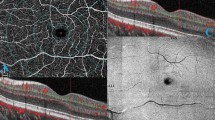

Macular OCTA slabs of the superficial vascular plexus (SVP), intermediate capillary plexus (ICP) and deep capillary plexus (DCP) were exported to Fiji ImageJ44 using standard slab and processing settings of the Spectralis OCTA module. Macular slabs were divided into an infero-macular und supero-macular portion by a line crossing the optic nerve head and the central avascular zone using a stitched overlay of the OCTA slab and a larger 30°x30° infrared image generated by the Spectralis device, in which the optic nerve head was visible. Afterwards large vessels in the SVP-slab and large vessel projection artifacts in the ICP and DCP were removed using a Hessian-based large vessel removal filter as previously published by our group37. Finally, images were binarized using the Otsu thresholding algorithm45 and hemispheric capillary densities of SVP (SCDhemi), ICP (ICDhemi) and DCP (DCDhemi) were calculated as the percentage of white pixels. Figure 4 summarizes relevant steps of OCTA image processing.

Representative OCTA slab processing workflow. white column: macular slabs were divided into an infero-macular und supero-macular portion and large vessels were removed using a Hessian-based large vessel removal filter. light grey column: binarized hemispheric superficial vascular plexus (SVP) slabs after large vessel removal. dark grey column: binarized hemispheric intermediate capillary plexus (ICP) slabs after projection artifact removal. black column: binarized hemispheric deep capillary plexus (DCP) slabs after projection artifact removal.